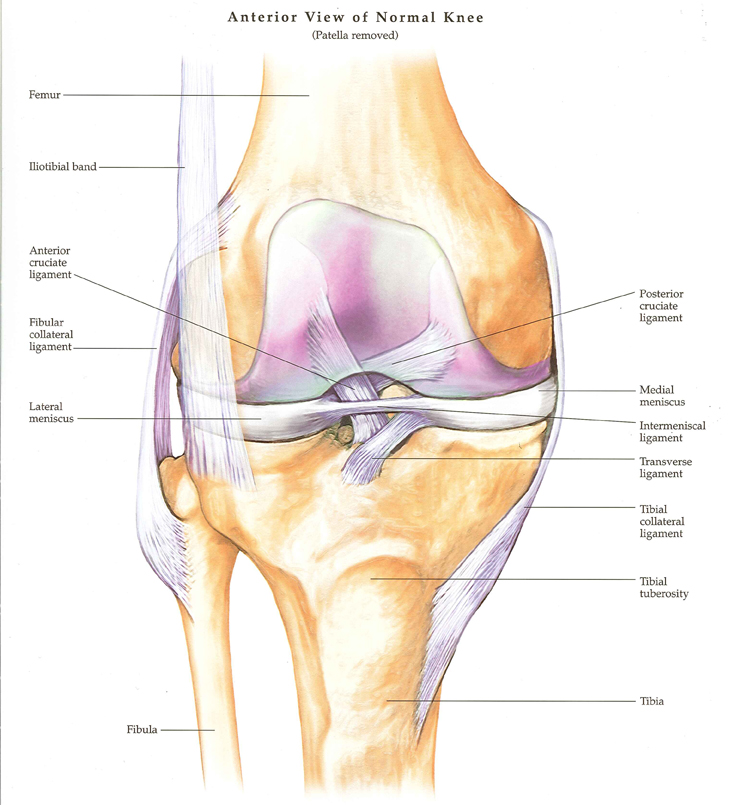

박상준 의원 병원위치, 진료시간, 연락처 등등이 궁금하면 클릭하세요. ^^ (당산 당산역 당산동 여의도 합정 목동 영등포 영등포구청 선유도 양평동 국회의사당 정형외과 야간진료 도수치료 통증의학과 박상준의원) 안녕하세요. 당산역 박상준의원에서 도수치료를 담당하고 있는 물리치료사 박호동입니다. 이번시간에는 무릎 앞쪽으로 통증이 있을 때 도움이 되는 운동방법에 대해 알려드릴까 해요. 장시간 걷거나, 계단을 오르거나, 앉았다 일어설 때, 무릎 앞쪽으로 통증을 호소하는 경우가 종종 있는데, 이런 경우, 보통 슬개골 주변근육의 과긴장으로 무릎에 압박이 증가해서 통증을 호소하게 됩니다. 그래서, 이번시간에는 무릎앞쪽에 있는 슬개골을 중심으로 관절주변을 부드럽게 해주고, 무릎안정에 도움이 되는 운동을 해보도록 하겠습니..